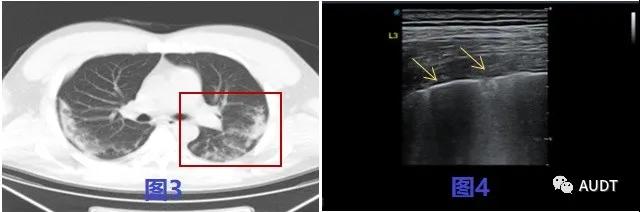

进展中期,图5-6 CT显示右肺下叶肺周处胸膜下可见大片状筛网状软组织影,图7 线阵探头显示相应肺周胸膜线欠连续,胸膜下可见长条样实变影,其内细支气管肺泡充气征,呈铺路石样改变,间质性病变征象显著,后伴大量B线。